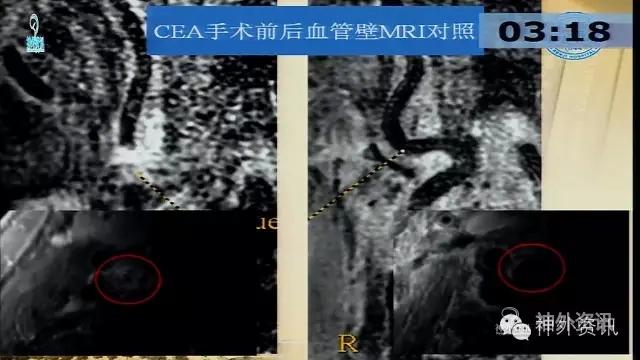

万杰清教授:慢性颈动脉闭塞再通技术及临床效果

擅长脑血管病的治疗研究工作,对动脉瘤性蛛网膜下腔出血的规范化、个体化治疗有独到之处,已成功治愈各种复杂性脑血管3000余例;擅长脑血管病的微创血管内介入和显微外科治疗,包括急性破裂出血的脑动脉瘤、脑血管畸形和硬脑膜动静脉瘘的栓塞治疗,以及颈动脉内膜切除和血管内支架治疗颈动脉狭窄预防脑梗死等。.曾获得仁济医院首届十佳青年,第二医科大学新长征突击手和优秀仁济人—白求恩式的好医生称号,2010仁济医院首届优秀青年临床骨干。分获上海市科技进步二等奖和三等奖。已发表论文30余篇,SCI收录7篇。